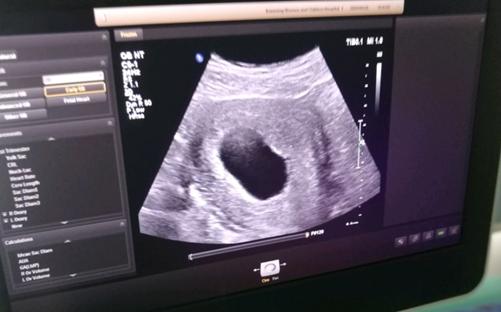

想知道自己是否有空囊的情况很简单。正常情况下,女性在怀孕2个月时再次检查时,可以清楚地看到胎儿和胎心。如果患有空囊病,在检查时不能看到孕妇自己体内里的胎儿和胎心,基本上可以诊断为空囊症。

怀孕公囊可自然流产6 ~ 8周,很少发育3个月以上,公囊可在怀孕40多天前发现。空囊可以自然流产,但女性以后要重新考虑,如果流产不完整,则要通过手术处理清宫。

6个月后再怀孕,孕期不要暴露在放射线下,远离环境污染,怀孕时不要有太大压力,紧张和压力会导致机体内分泌失衡,对胚胎的健康发育有一定影响。女性应该在怀孕8周左右做b超,确认是否存在胎心胎儿。